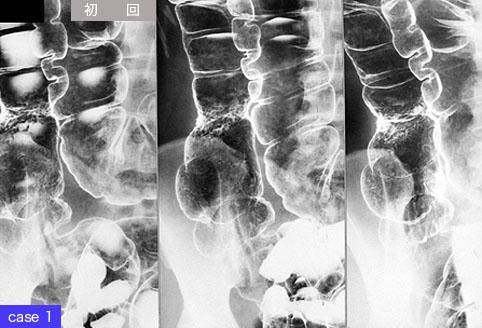

疾病(病理主体)的分类肿瘤样病变/炎症性息肉病

部位(按器官分)大肠/升结肠

检查方法X线

肿瘤最大直径1~9